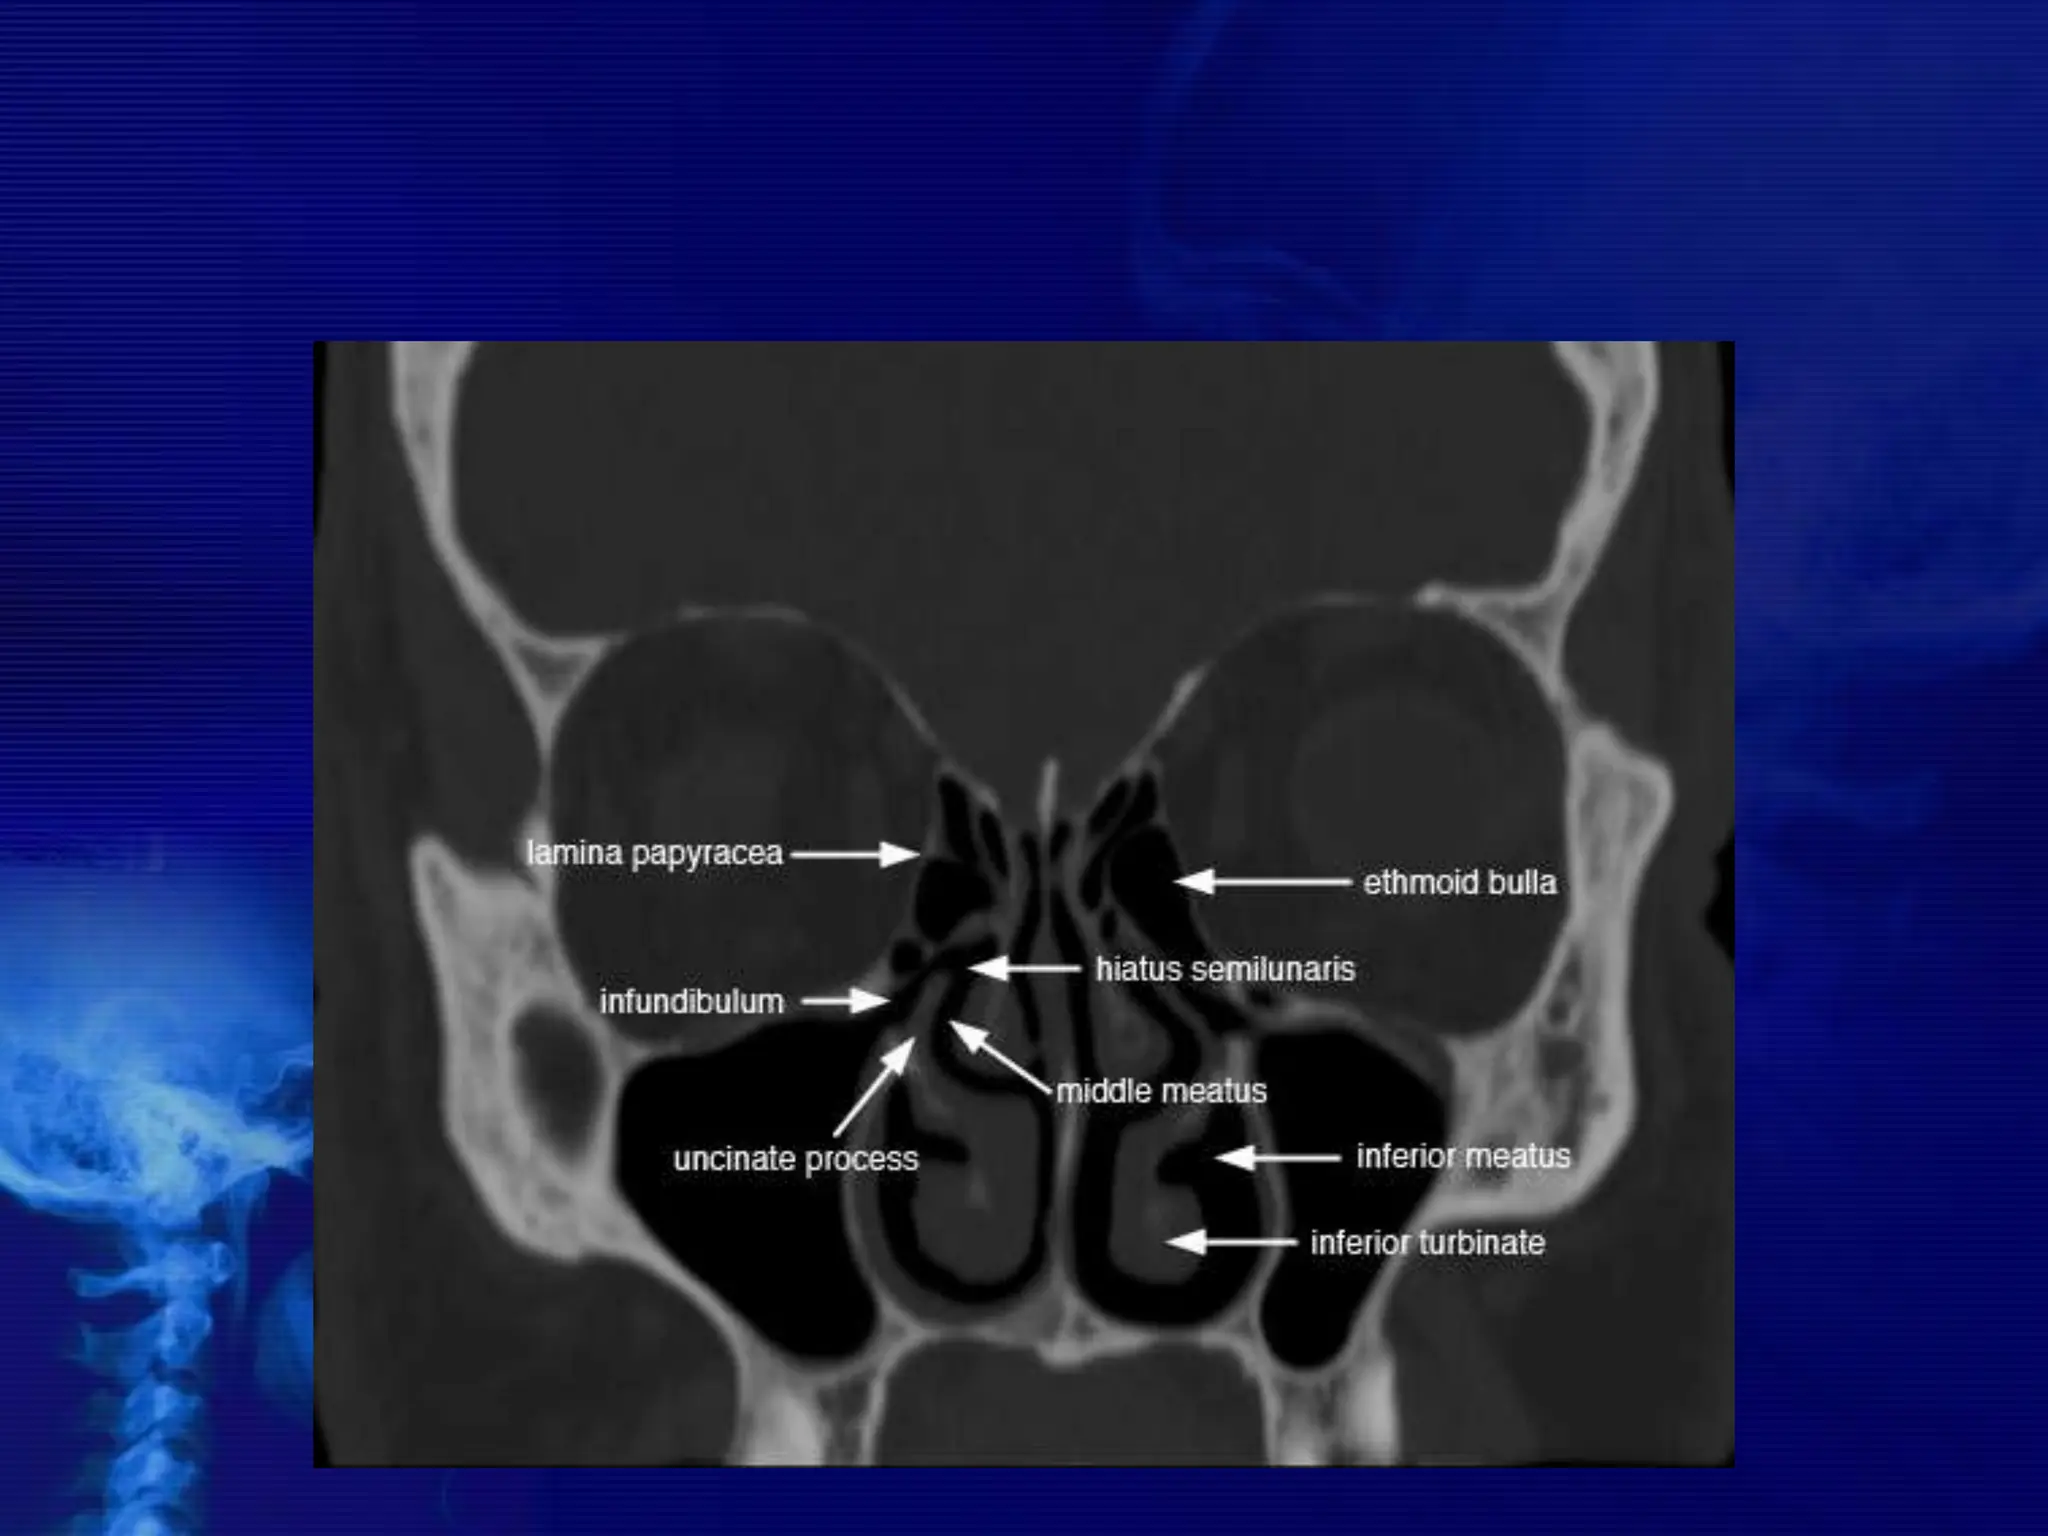

Osteomeatal unit

• The osteomeatal unit (OMU) includes the (1) maxillary

sinus ostium, (2) ethmoid infundibulum, (3) anterior

ethmoid air cells, and (4) frontal recess.

• The OMU is the key factor in the pathogenesis of chronic

sinusitis.

The Lateral Wall of Nasal Cavity

Marked by 3

projections:

• Superior concha

• Middle concha

• Inferior concha

• The space below

each concha is

called a meatus.

1. Inferior meatus:

nasolacrimal duct

2. Middle meatus:

• Maxillary sinus

• Frontal sinus

• Anterior ethmoid

sinuses

3. Superior meatus:

posterior ethmoid

4. Sphenoethmoidal

recess: sphenoid

sinus

• #8 Figure 1 (A, B): (A) Coronal CT scan shows the osteomeatal complex which comprises of - infundibulum (dotted line), hiatus semilunaris (asterisk), maxillary ostium (arrow) and Ethmoidal bulla (EB). MT-middle turbinate, LP-lamina papyracea. (B) Coronal CT images reveals a prominent agger nasi cell (A) inferior and lateral to the nasofrontal recess (solid curved line). The medial relationship of the recess is formed by the middle turbinate (MT)